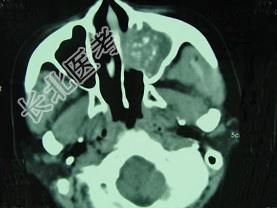

- 单项选择题男,41岁, 左侧鼻腔胀痛半年余,CT检查如图, 最可能诊断为 ( )

A、出血坏死性息肉

B、化脓性鼻窦炎

C、变应性鼻窦炎

D、真菌性鼻窦炎

E、上颌窦癌